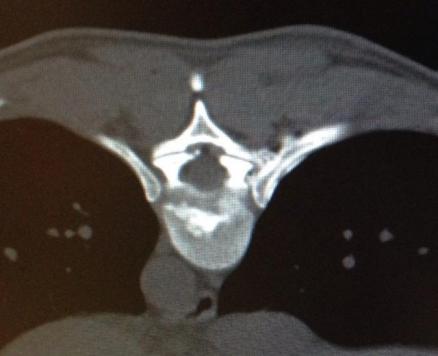

Hierbei wird unter Röntgenkontrolle eine dünne Nadel an die schmerzhaften Gelenke der Wirbelsäule geführt. Die anschließende Verödung der Nerven, welche die Schmerzen verursachen, erfolgt über eine Glasfaser.

Der Eingriff dauert etwa 15 Minuten und wird in örtlicher Betäubung und leichter Sedierung durchgeführt. Gerade die schwierige Behandlung der Ileosacralgelenke ist mit dieser Methode mit gutem Erfolg anzuwenden und vermeidet unnötiger Versteifungsoperationen. Er Effekt hält bis zu 4 Jahren an.

Wer die Wirbelsäule nicht nur aus Lehrbüchern, sondern auch aus dem OP kennt, weiß um die Arthrose der Wirbelgelenke. Diese sehen gänzlich anders aus als im Anatomiebuch. Darum haben wir eine Methode entwickelt, die Gelenke im Abstand der Verödungsorte von jeweils 2 mm schmerzfrei zu machen.